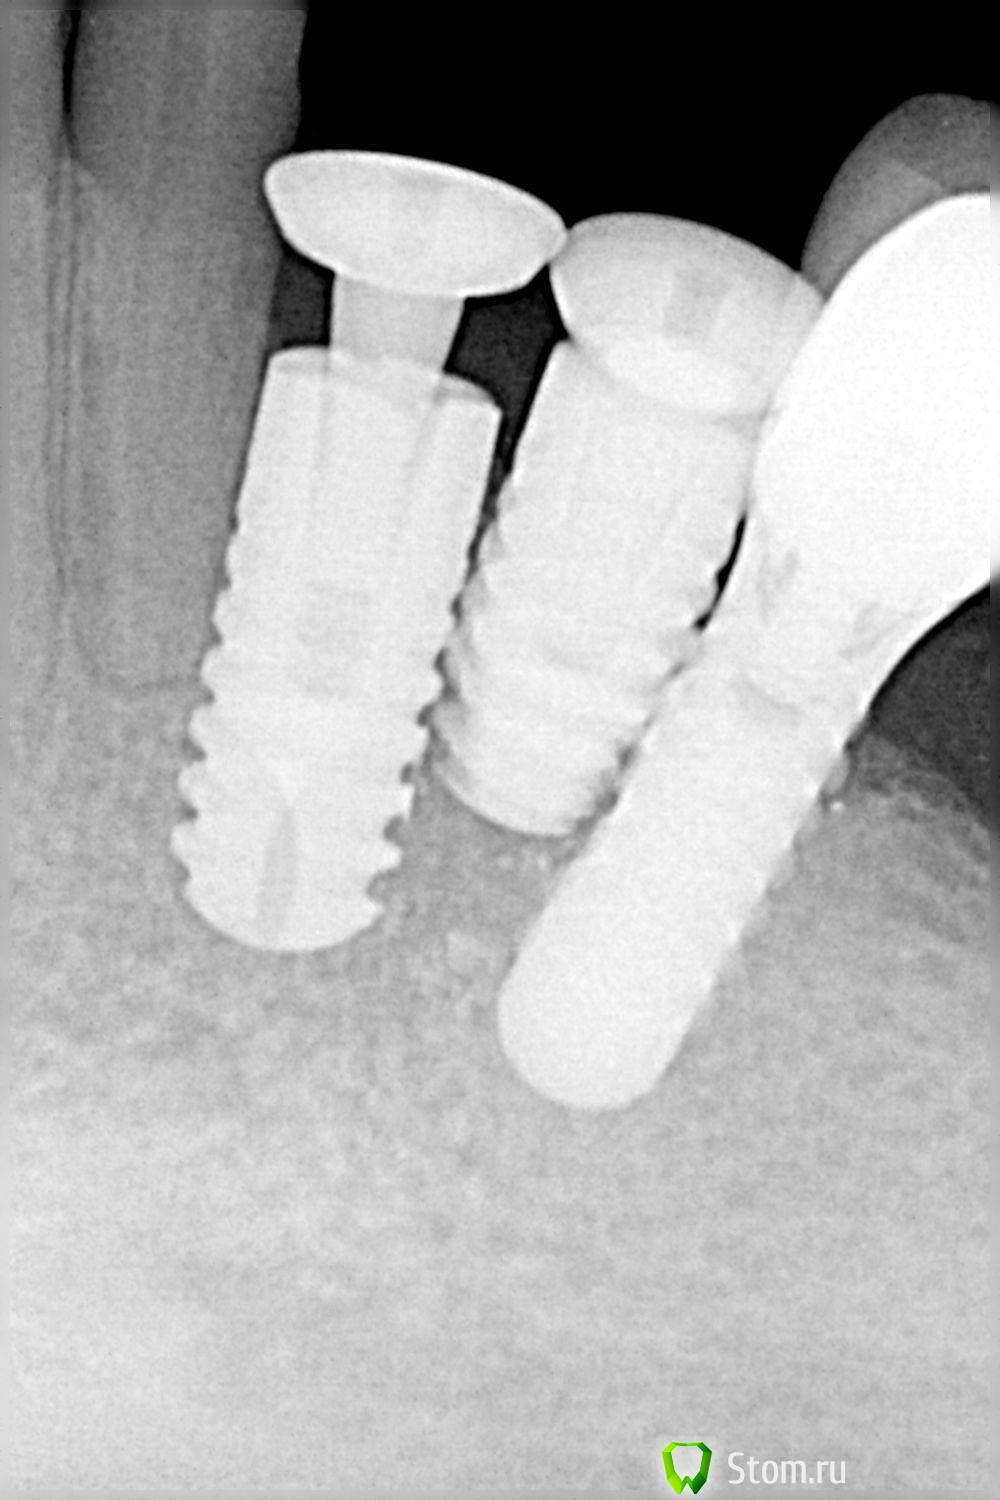

Sib-oboima Опубликовано 23 марта, 2012 Автор Поделиться Опубликовано 23 марта, 2012 Была на днях пациентка, протезировал год назад на имплантах, записалась ко мне на прием. Ну думаю на осмотр, посмотрюкак дела, а там , рассказывает во время отпуска моего, она записалась на удаление двух зубов, сразу ей хирург поставил 2 импланта . Ссылка на комментарий

Sib-oboima Опубликовано 23 марта, 2012 Автор Поделиться Опубликовано 23 марта, 2012 (изменено) Сильное оголение на штаумане, но не подвижен. Даже не знаю что делать, выкручивать это все, про пластику заикнулся пациентке, говорит что хирург делал , выкрутить один, делать времяшку, наблюдать, у меня каша в голове Изменено 23 марта, 2012 пользователем Sib-oboima Ссылка на комментарий

Doc Опубликовано 23 марта, 2012 Поделиться Опубликовано 23 марта, 2012 Была на днях пациентка, протезировал год назад на имплантах, записалась ко мне на прием. Ну думаю на осмотр, посмотрюкак дела, а там , рассказывает во время отпуска моего, она записалась на удаление двух зубов, сразу ей хирург поставил 2 импланта . Просто НЕТ СЛОВ!!!! Один мат... Хочется спросить "ДОКОЛЕ?!!" До каких пор у нас в стране будут приличных врачей засуживать из-за какой-нибудь ерунды, а вот такие вот уроды (и моральные, и умственные, и физические!) будут торговать имплантами на вес и процветать?!! 1 Ссылка на комментарий

Doc Опубликовано 23 марта, 2012 Поделиться Опубликовано 23 марта, 2012 Сильное оголение на штаумане, но не подвижен. Даже не знаю что делать, выкручивать это все, про пластику заикнулся пациентке, говорит что хирург делал , выкрутить один, делать времяшку, наблюдать, у меня каша в голове Ну здесь только два пути: правильный (все убрать, пластика и все заново), паллиативный - лепить что-то хоть на один из них до тех пор, пока все это не развалится и тогда переходить к пункту первому. На Вашем месте я бы придерживался правильного пути, иначе потом и Ваш нормальный имплантат с коронкой полетит и Вы еще и отвечать будете за всю эту вакханалию. И думаю, что в данном случае даже жалеть коллегу-морального урода нет никакой необходимости. Нужно честно сказать пациентке, что все, что ей поставили, нужно вынимать, иначе не только имплантаты потеряет, но и кость, а еще и зуб может пойти прицепом. Кстати, зуб-то на перкуссию пока не реагирует? Если хирург из Вашей же клиники, тогда тупо показать снимок главному врачу и самоустраниться, пусть сам разбирается. Ссылка на комментарий

Doc Опубликовано 23 марта, 2012 Поделиться Опубликовано 23 марта, 2012 Если это тот же хирург, который ставил имплантаты и в первом случае (первое сообщение данной темы), то мне кажется, что нужно предложить главному врачу гнать его взашей, пока не поздно. Достаточно уже тех снимков, которые висят в данной теме, чтобы руки оборвать этой ходячей жадной глупости. Ссылка на комментарий